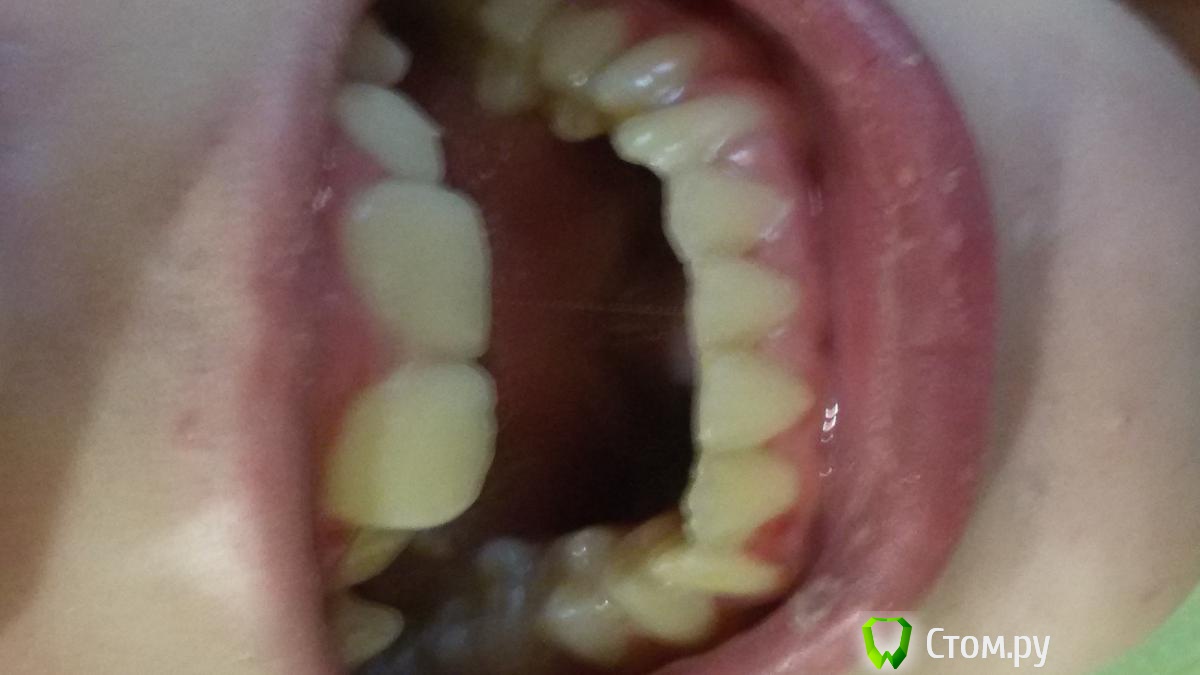

Элько Опубликовано 21 августа, 2014 Поделиться Опубликовано 21 августа, 2014 Здравствуйте! Девочка 12.5 лет . Доктор, сделав панорамный снимок, дала направление на удаление 24 зуба и через два месяца на прием с дальнейшим удалением с другой стороны . Так как клыкам нет места совсем на челюсти они лезут сверху вторым рядом. над 24 уже прорезался а с другой стороны еще нет. Подскажите удаление здоровых коренных зубов как в дальнейшей жизни скажется? И возможны ли другие варианты лечения. Ссылка на комментарий

Ayrat_zub Опубликовано 21 августа, 2014 Поделиться Опубликовано 21 августа, 2014 Здравствуйте! Девочка 12.5 лет . Доктор, сделав панорамный снимок, дала направление на удаление 24 зуба и через два месяца на прием с дальнейшим удалением с другой стороны . Так как клыкам нет места совсем на челюсти они лезут сверху вторым рядом. над 24 уже прорезался а с другой стороны еще нет. Подскажите удаление здоровых коренных зубов как в дальнейшей жизни скажется? И возможны ли другие варианты лечения.упражнение для шеи решили устроить?)) снмики первернутые как попало) можно буз удаения 4-ок, еще одного снимка не хватает Ссылка на комментарий

Ayrat_zub Опубликовано 22 августа, 2014 Поделиться Опубликовано 22 августа, 2014 Я не знаю почему они в разные стороны у меня все ровно было а выгрузилось так .А какой еще нужен снимок? и как без удаления ? Я так понимаю с удалением проще все поставить на место, но как это аукнется в дальнейшем? снимок ТРГ, и кт в области верхних клыков, удалить скорее всего рпидется, но не 4-ки, а зубы мудрости, хотя на верхней челсюти есть варианты) сделайте более четкие фото) по поводу ортодорнта-http://forum.stom.ru/topic/4747-posovetuite-ortodonta-v-gorode-n/ Ссылка на комментарий

Фазлиев Азат Ильдусович Опубликовано 23 августа, 2014 Поделиться Опубликовано 23 августа, 2014 Здравствуйте! Девочка 12.5 лет . Доктор, сделав панорамный снимок, дала направление на удаление 24 зуба и через два месяца на прием с дальнейшим удалением с другой стороны . Так как клыкам нет места совсем на челюсти они лезут сверху вторым рядом. над 24 уже прорезался а с другой стороны еще нет. Подскажите удаление здоровых коренных зубов как в дальнейшей жизни скажется? Лечение однозначно без удаления 4ок! Ссылка на комментарий